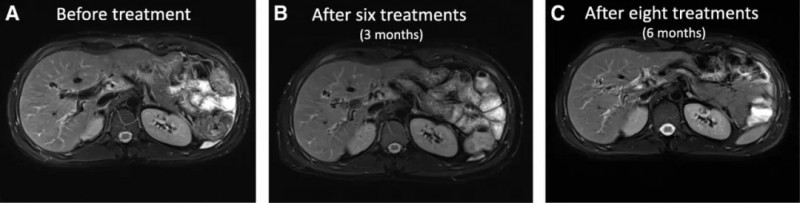

结果显示:从MRI图像中,我们可以看到淋巴结明显缩小,直观地看到随着Vδ2T细胞输注次数的增加,患者的淋巴结转移逐渐消失(详见下图)。

▲图源“BMJ”,版权归原作者所有,如无意中侵犯了知识产权,请联系我们删除